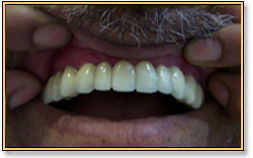

Full Mouth Replacement with Implants

This 77 year old patient was wearing upper removable dentures for the past few years. He had occasional difficulty while chewing, sneezing and coughing. The dentures used to come out and were a huge

embarrassment. Having lived a comfortable life for most of his age, it was very disheartening for him.

The first photograph shows the preoperative condition of the mouth. The second picture shows the abutments in place after the second stage surgery. The last picture is after the upper arch was completed with Metal Ceramic Bridges.